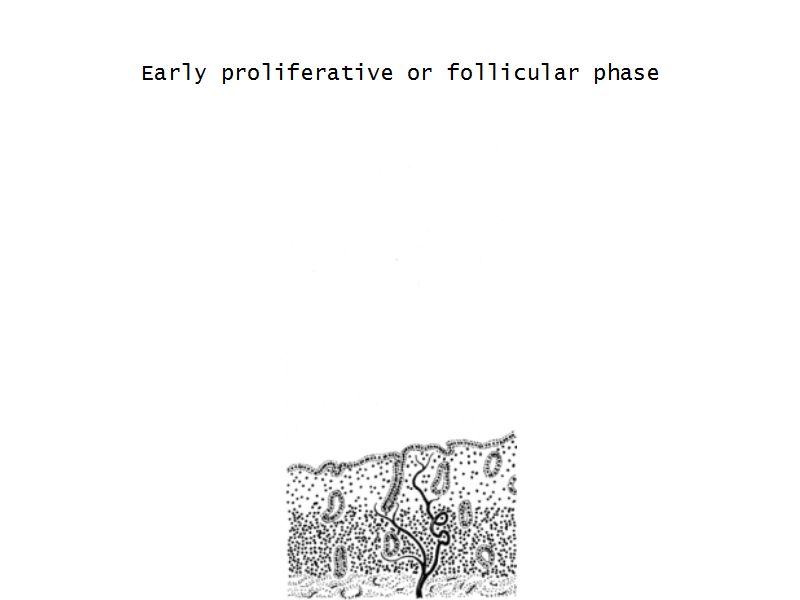

Menstrual cycle

- Follicular phase

Follicular phase

- Epithelium reform

- Proliferation of

- Glands

- Connective tissue

- Blood vessels

- Glands become coiled

- Helical arteries 2/3 into endometrium